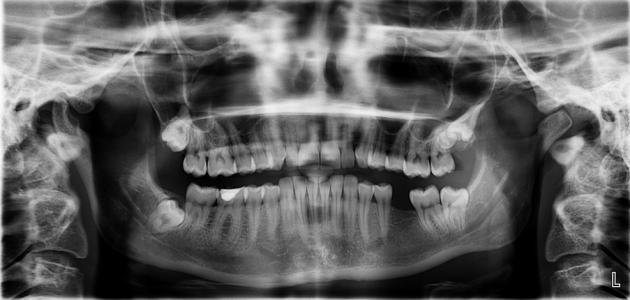

يُعتبر التصوير بالأشعة السينية من الأدوات التشخيصية الضرورية للعديد من إجراءات طب الأسنان، وخاصة حالات الطوارئ، وعادةً ما يُنصح بتأجيل الأشعة السينية السنوية والروتينية إلى ما بعد الولادة، وبالنسبة لأضرار أشعة الأسنان للحامل، فإنّه ووفقًا للكلية الأمريكية للأشعة لا توجد أشعة سينية تشخيصية لها جرعة إشعاعية كبيرة بما يكفي لإحداث تأثيرات ضارة للجنين، كما أنّ الجمعية الأمريكية لطب الأسنان اعتبرت أنّ أخذ صورة أشعة للأسنان أثناء فترة الحمل آمنة، بشرط اتخاذ إجراءات الحماية والوقاية اللازمة، وتجدر الإشارة إلى أنّه لا يوجد أي دليل يشير إلى تضرر الجنين في حال زيارة طبيب الأسنان خلال الثلث الأول من الحمل، ولكن يُفضل تأجيل أي علاج سني غير طارئ خلال هذه الفترة من الحمل إلى ما بعد الولادة، وذلك لتجنب خطر الولادة المبكرة، والاستلقاء لفترة طويلة على الظهر عند طبيب الأسنان.[١]